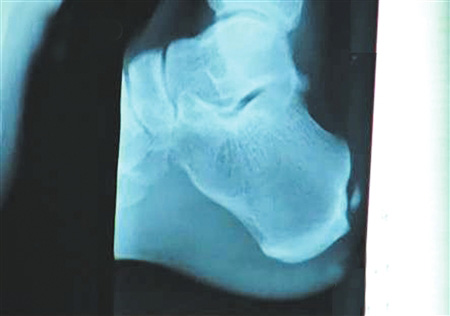

组图:刘翔跟腱手术全过程揭秘

手术要取出的钙化物就在这里。 图片来源:华西都市报

北京时间12月6日凌晨,备受关注的中国飞人刘翔在休斯顿赫曼纪念医院的跟腱手术成功结束。